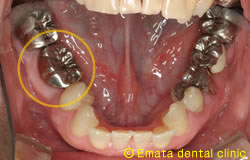

右上の虫歯が大きく、また右下の奥歯が根の病気が大きく抜歯になりました。 親知らずや内側に倒れた不必要になった歯があったので移植をおこないました。